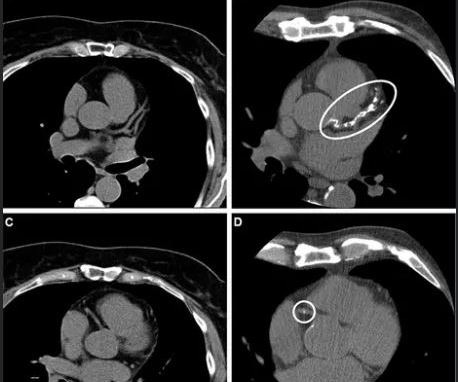

Magdalena Seng, MD, presents survey findings at RSNA 2024 showing the attitudes and perceptions of medical students when it comes to careers in radiology.